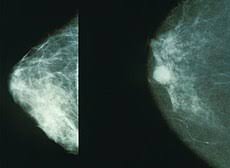

Breast Biopsy Johns Hopkins Medicine from www.hopkinsmedicine.org Typical features of inflammatory breast cancer include: Breast cancer is cancer that develops from breast tissue. New lump in the breast or underarm (armpit) thickening or swelling of part of the breast irritation or dimpling of breast skin Early detection is key in treating breast cancer symptoms. A painless, hard mass that has irregular edges is more likely to be cancer, but breast cancers can be tender, soft, or round. Persistent coughing and other symptoms similar to those produced by the common cold and flu. For the majority of people with metastatic breast cancer, the metastases represent a recurrence of a breast cancer which you had in the past. Some warning signs of breast cancer are— new lump in the breast or underarm (armpit).